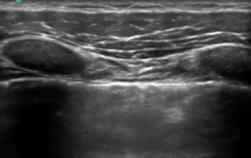

HFLトランスデューサー付き肺の画像